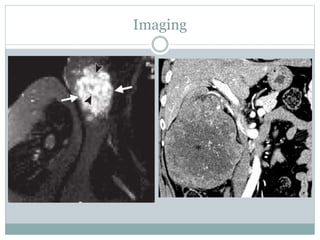

Imaging

• #9 MRI shows high signal intensity on the T2-weighted image. Serpentine areas of low signal intensity on the T2-weighted image (arrowheads in c) suggest a high-flow vessel component. Coronal contrast-enhanced computed tomography scan of abdomen reveals large, heterogeneous, enhancing right renal mass with prominent internal vascular structure. Central, non-enhancing portions represent central tumor necrosis (asterisk).